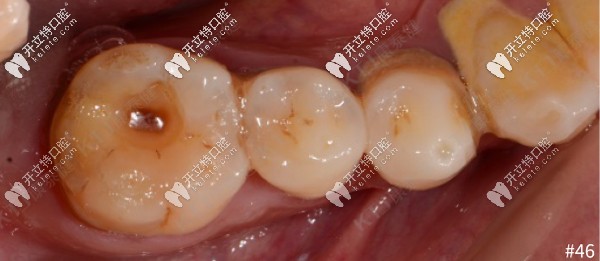

2、46牙體預(yù)備:覆蓋遠(yuǎn)舌尖的高嵌體洞型預(yù)備,IDS,保證洞型邊緣的釉質(zhì)層連續(xù),為嵌體粘結(jié)提供良好的封閉區(qū)。

46牙體備洞